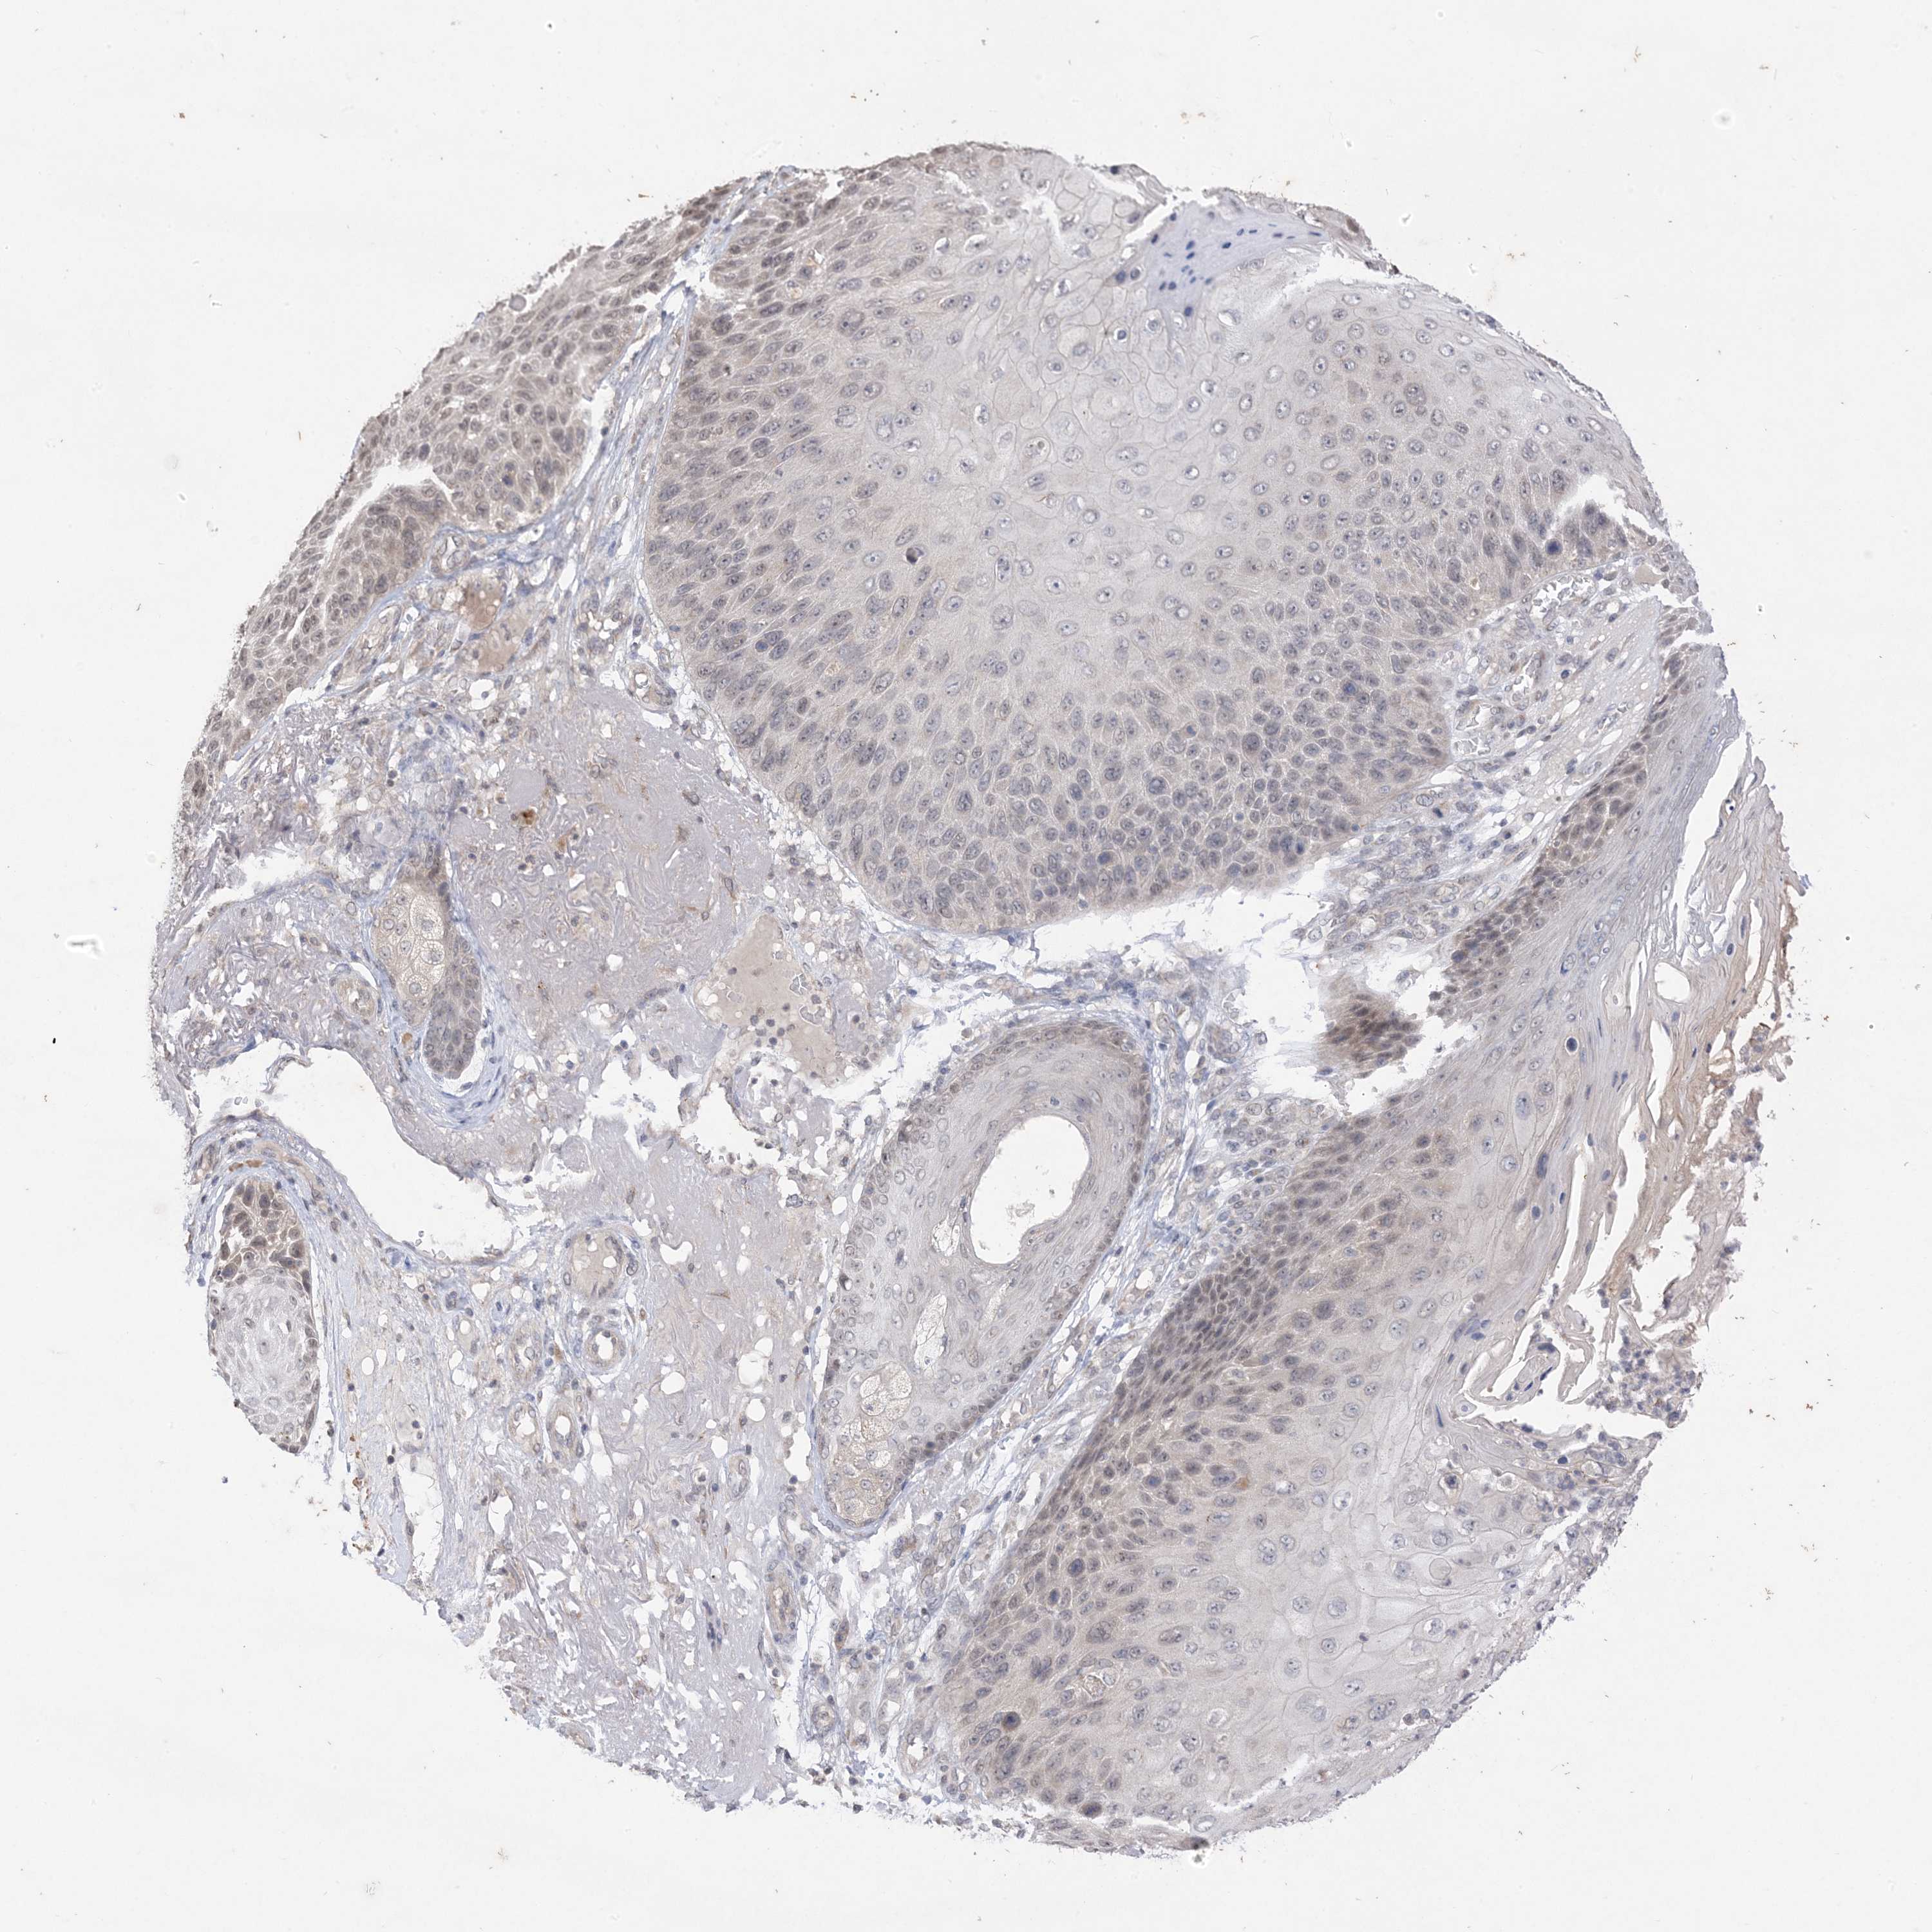

CANCER SKIN CANCER Show tissue menu

Basal cell and squamous cell cancer

SKIN CANCER - Protein expressioni

A mouse-over function shows sample information and annotation data. Click on an image to view it in a full screen mode. Samples can be filtered based on level of antibody staining by selecting one or several of the following categories: high, medium, low and not detected. The assay and annotation is described here.

Each image is clickable and will lead to virtual microscopy that enables deeper exploration of all samples and also displays staining intensity scores, fraction scores and subcellular localization as well as patient and tissue information for each sample.

Antibody HPA038395

Antibody HPA038396

Antibody CAB032519

Basal cell carcinoma

Squamous cell carcinoma, NOS

Squamous cell carcinoma, metastatic, NOS